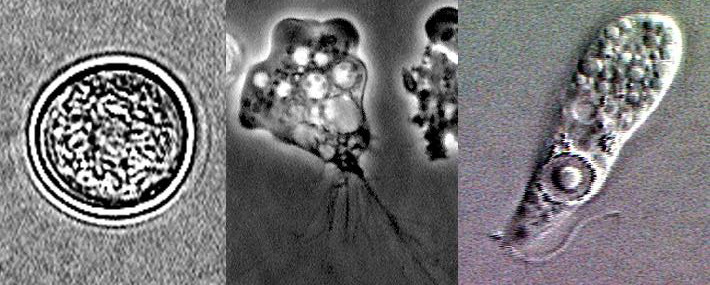

Stadi del ciclo vitale di N. fowleri, da sinistra: cisti, trofozoide e forma flagellata (Wikimedia)

N. fowleri prosegue il proprio viaggio lungo le terminazioni delle cellule olfattive e, di solito entro una decina di giorni da quando era stata inalata, riesce infine a raggiungere il cervello dove la sua attività viene ulteriormente stimolata dalla grande disponibilità di acetilcolina. Qui l’ameba produce particolari molecole che fanno a pezzi i neuroni, in modo che se ne possa nutrire. Inizia a moltiplicarsi e a trasformarsi, sviluppando minuscole ventose che si attaccano e distruggono le membrane delle cellule, nutrendosi di parte del loro contenuto.

Anche se viene chiamata ameba mangia-cervello, N. fowleri non è tecnicamente un’ameba vera e propria, ma alterna forme flagellate ad ameboidi: in sostanza ci assomiglia molto in alcuni stadi del suo ciclo vitale. Come altri suoi simili, N. fowleri è ghiotta di batteri dei quali va a caccia per spezzarli e nutrirsene. In natura vive solamente in acqua dolce e prolifera negli stagni, nei laghi, nelle fonti termali e talvolta in tratti di fiumi e torrenti dove la corrente è tranquilla. Può però essere trovata anche nelle tubature degli acquedotti, nelle fontane e nelle piscine, in particolare se l’acqua non è trattata adeguatamente per essere resa potabile attraverso l’aggiunta di cloro.